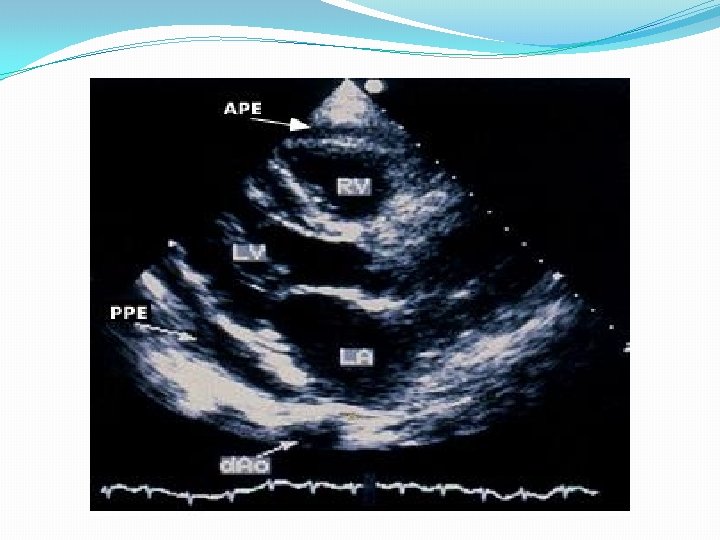

Echocardiogram The echocardiogram is often normal in patients with the clinical syndrome of acute pericarditis unless it is associated with a pericardial effusion. While the finding of a pericardial effusion in a patient with known or suspected pericarditis supports the diagnosis, the absence of a pericardial effusion or other echocardiographic abnormalities does not exclude it.

Echocardiography should be performed in all cases, and should be considered on an urgent basis if tamponade is suspected. Even a small effusion can be helpful in confirming the diagnosis of pericarditis, although the absence of an effusion does not exclude the diagnosis. In addition, echocardiography can be particularly helpful if purulent pericarditis is suspected, if there is concern about myocarditis, or if there is chest x-ray evidence of cardiac enlargement, particularly if this is a new finding.